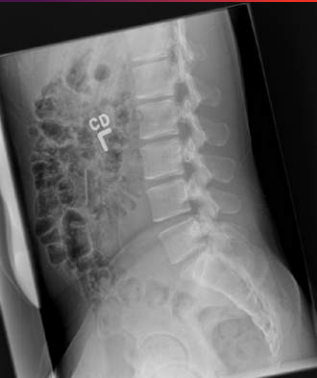

MUSICA3+ Skeleton+

Diagnostisk kvalitet – også ved store patienter

Lav penetration og høj scatter ved store og bariatriske patienter kan gøre columna-, bækken- og ribbensoptagelser diagnostisk utilstrækkelige. Skeleton+ fremhæver netop de kritiske detaljer, der ellers går tabt.

- Skarpere trabekulære strukturer og tydeligere hvirvelafgrænsning

- Egnet til columna, bækken og ribben

- Diagnostisk billedkvalitet uanset patientstørrelse